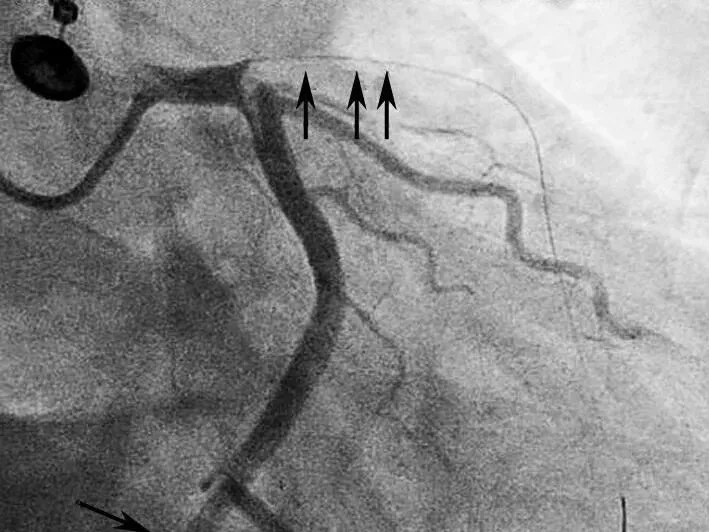

给予双联抗血小板、调脂、控制心率、抗心衰及泼尼松龙60mg每日1次,并皮下注射依诺肝素强化抗凝,1周后复查心脏超声(图2),发现右房内疑似血栓影完全消失,患者也无低氧、咯血等肺栓塞临床表现。后完成CAG +光学相干成像(OCT)检查(图3),提示:左优势型,前降支近段管腔不规则发白,考虑血栓影,管腔分支稀少,血流TIMI 3级;回旋支远段节段性狭窄达90%,血流TIMI 2级;右冠细小。

图2 抗凝前后超声心动图对比

A图为入院心脏超声心尖四腔切面,可见右房内疑似血栓影,舒张期可进入右心室内;B图为抗凝治疗1周后复查,可见右房内血栓消失